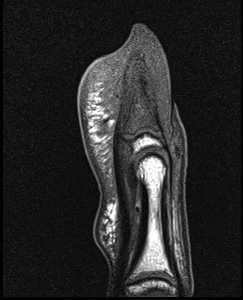

Figure 3 for case Osteoid osteoma ( RID4005 )

Figure 3